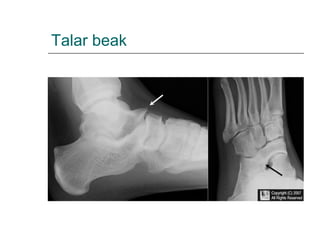

Coalición tarsiana: tipos

Diferencia??

Talar beak

 Rx axial de calcani per veure el

calcani

Dieu el que veieu.

• #35 The talar beak sign is seen in cases of tarsal coalition, and refers to a superior projection of the distal aspect of the talus. It is most frequently encountered in talocalcaneal coalition 1-2. It is thought to result from abnormal biomechanic stresses at the talonavicular joint. Most common coalitions (90% of total) are Calcaneous and navicular (calcaneonavicular) Calcaneous and talus (talonavicular) - See more at: http://www.learningradiology.com/archives2007/COW%20281-Talar%20beak/talarbeakcorrect.html#sthash.j59SHoxF.dpuf